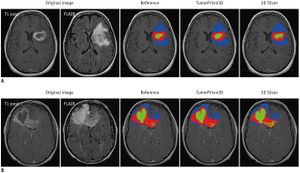

Publication: Nat Neurosci. 2017 Oct;20(10):1329-41. PMID: 28805815 | PDF Authors: Chow RD, Guzman CD, Wang G, Schmidt F, Youngblood MW, Ye L, Errami Y, Dong MB, Martinez MA, Zhang S, Renauer P, Bilguvar K, Gunel M, Sharp PA, Zhang F, Platt RJ, Chen S. Institution: Department of Genetics, Yale University School of Medicine, New Haven, CT, USA. Abstract: A causative understanding of genetic factors that regulate glioblastoma pathogenesis is of central importance. Here we developed an adeno-associated virus-mediated, autochthonous genetic CRISPR screen in glioblastoma. Stereotaxic delivery of a virus library targeting genes commonly mutated in human cancers into the brains of conditional-Cas9 mice resulted in tumors that recapitulate human glioblastoma. Capture sequencing revealed diverse mutational profiles across tumors. The mutation frequencies in mice correlated with those in two independent patient cohorts. Co-mutation analysis identified co-occurring driver combinations such as B2m-Nf1, Mll3-Nf1 and Zc3h13-Rb1, which were subsequently validated using AAV minipools. Distinct from Nf1-mutant tumors, Rb1-mutant tumors are undifferentiated and aberrantly express homeobox gene clusters. The addition of Zc3h13 or Pten mutations altered the gene expression profiles of Rb1 mutants, rendering them more resistant to temozolomide. Our study provides a functional landscape of gliomagenesis suppressors in vivo. "Raw image stacks were processed using Osirix or 3D Slicer tools. Rendering and quantification were performed using 3D Slicer." Funding:

Autochthonous brain tumorigenesis induced by an AAV-mediated CRISPR library. (a) Schematics of direct in vivo AAV-CRISPR GBM screen design. Top: AAV-mTSG library design, synthesis and production. Bottom: stereotaxic injection of AAV library and subsequent analysis. HPF, hippocampus; LV, lateral ventricle. (b) MRI sections show brain tumors in AAV-mTSG injected mice but not in PBS- or AAV-vector-injected mice. Matching sections are shown. Arrowheads indicate brain tumors. Scale bar, 5 mm. (c) MRI-based volumetric quantification of time-matched tumor size ± s.e.m. Two-tailed Welch’s t test, t17 = 2.62, P = 0.018, mTSG vs. vector or PBS (PBS, n = 2 mice; vector, n = 6; mTSG, n = 18). (d) Kaplan-Meier curves for overall survival (OS) of mice injected with PBS (n = 5), AAV-vector (n = 24) or AAV-mTSG library (n = 56). OS for PBS and vector groups are both 100%; the curves are dashed and slightly offset for visibility; dpi, days postinjection. Log-rank (LR) test, P < 2.20 × 10−16, mTSG vs. vector or PBS. |